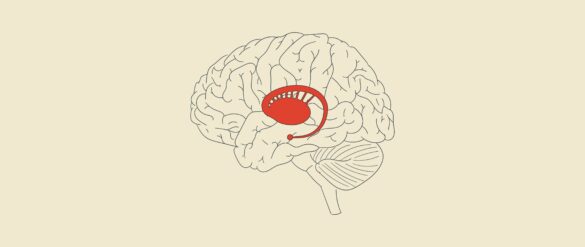

Núcleo accumbens: Regulador del placer y las recompensas

El núcleo accumbens es una estructura cerebral clave en la regulación del placer y las recompensas en el cerebro humano. Ubicado dentro del cerebro, en regiones comúnmente denominadas como áreas subcorticales, el núcleo está estrechamente involucrado en la experiencia de la gratificación y la motivación….